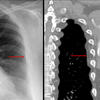

Aortic nipple

Date: 03/29/2014

Views: 5871

Ex 1 CT

Date: 03/23/2004

Views: 5378